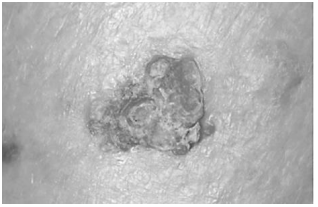

A imagem abaixo mostra uma lesão localizada

na região malar direita de um idoso trabalhador

rural do Vale do São Francisco:

Um homem de 76 anos, trabalhador rural desde a juventude, procura atendimento devido a uma lesão facial que vem aumentando de tamanho nos últimos meses. Refere queimaduras solares repetidas, nunca fez uso regular de protetor solar e tem múltiplas áreas de queratose actínica.

Ao exame, observa-se lesão hiperqueratótica e ulcerada, de bordas endurecidas de 1,8cm. Não há linfonodos cervicais palpáveis.